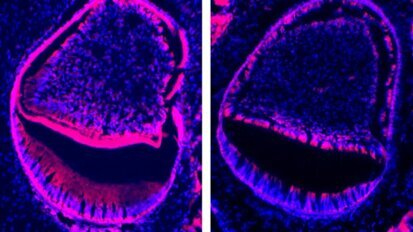

Coenzyme Q10 : une molécule naturelle améliore l’état gingival

Le coenzyme Q10 est synthétisé par le foie humain dès la naissance. Sans lui, pas de vie cellulaire possible. L’alimentation ...